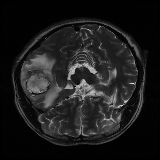

We obtain a subject-wise mean Dice score of 32.94% without any post-processing. By using a simple post-processing with erosion and dilation with filters, this number improves to 48.20% mean Dice score. In comparison, a similar study conducted by [3] consisting of a multitude of algorithms including AnoVAEGAN [4] and f-AnoGANS, obtained a best mean score of 27.8% Dice after post-processing by f-AnoGANS. Before post-processing the best method was Constrained AutoEncoder [8] with a score of 9.7% Dice. An exhaustive list is presented in Table 1. Figure 4 shows sample images of our results.

We obtain a subject-wise mean Dice score of 63.67% for the brain tumor segmentation. Utilizing a simple post-processing scheme of erosion and dilation with filter, we improve our mean Dice score to 68.01%. Figure 4 shows samples generated by our ASC-Net and Table 2 shows our before and after post-processing results. We attempted to apply f-AnoGANs [34] by following their online instructions and failed to generate good reconstructions as shown in Figure 5. The failure of AnoGANs in the reconstruction brings to light the issue with the regeneration based methods and the complexity and stability of GAN-based image reconstruction.

We obtain a slice-wise mean Dice score of 32.24% for this liver lesion segmentation, which improves to 50.23% by using a simple post processing scheme of erosion and dilation with filter. Sampled results are shown in Fig. 4. Compared with [42], which obtains a mean Dice score of 40.78% and a standard deviation of 0.43%, we improve the mean Dice score by almost 10%, but has a much larger standard deviation. Unlike [42], where the network is pre-trained on a artificial tumor dataset, and hence the pipeline customized for tumor segmentation, our method do not need such information beforehand. We notice that our standard deviation for BraTS dataset is similar to [27]. This is because novelty/anomaly detection algorithms without a pre-defined task would suffer from the co-morbidities issues discussed in Section 5.